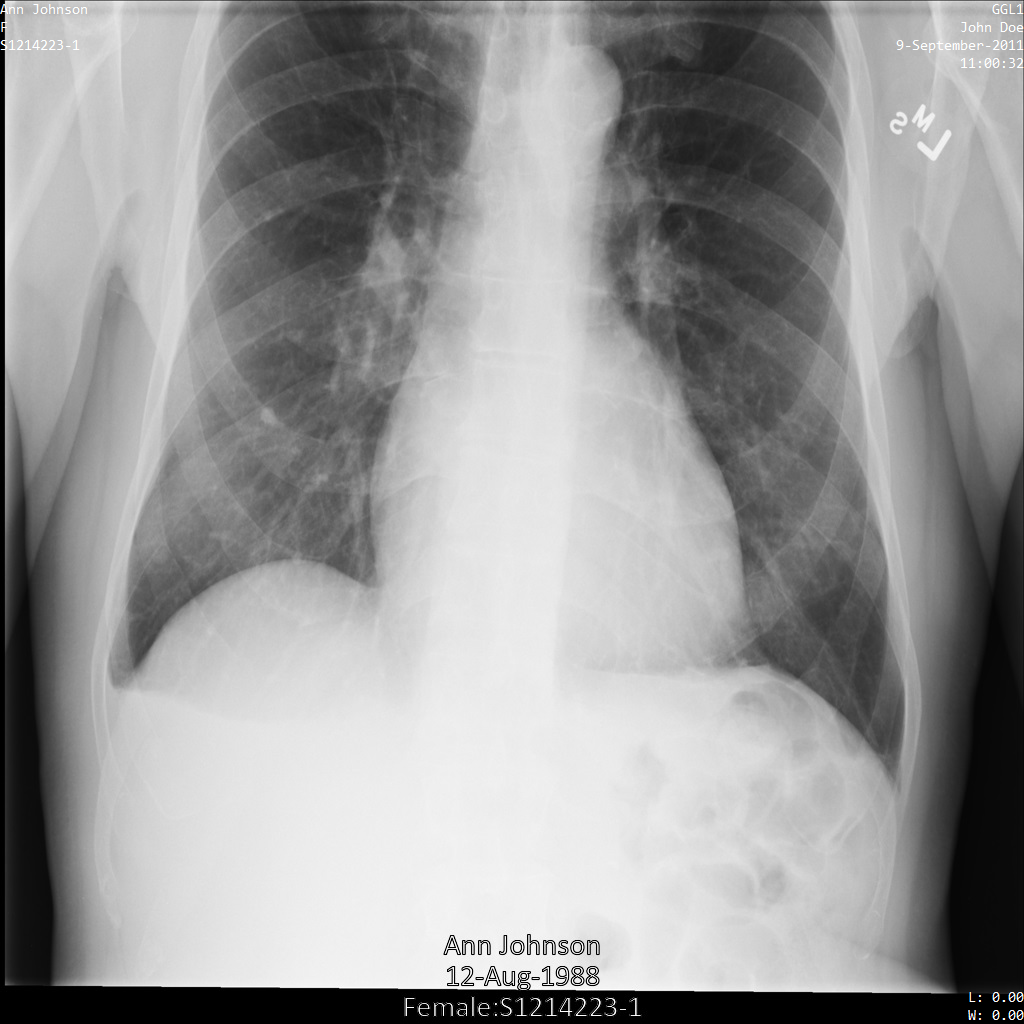

以下の各セクションでは、DICOM データを匿名化するさまざまな方法について、例を示しています。また、それぞれの例で匿名化された出力画像を示しています。各例では、入力として以下の元画像を使用しています。

各匿名化オペレーションからの出力イメージをこの元のイメージと比較して、オペレーションの効果を確認できます。

Cloud Healthcare API に画像を送信すると、画像は次のように表示されます。画像の上部隅に表示されているメタデータは削除されていますが、画像の下部にある焼き付き保護対象保健情報(PHI)は残ります。焼き付きテキストも削除するには、画像の焼き付きテキストを削除するをご覧ください。